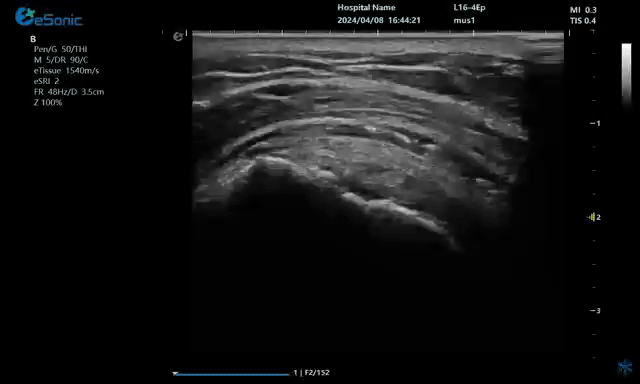

注射药物